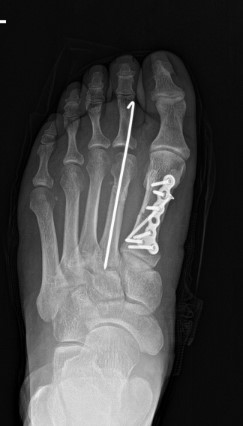

Preoperative Imaging

An X-ray of the right foot confirmed fractures of the first and second metatarsals.

The fractures were reduced and temporarily stabilized with K-wires.

Definitive fixation was achieved using titanium plates and screws.

Fluoroscopic imaging confirmed anatomic alignment and stable fixation.

Postoperative internal fixation with plate and screws of a fracture of the first metatarsal.